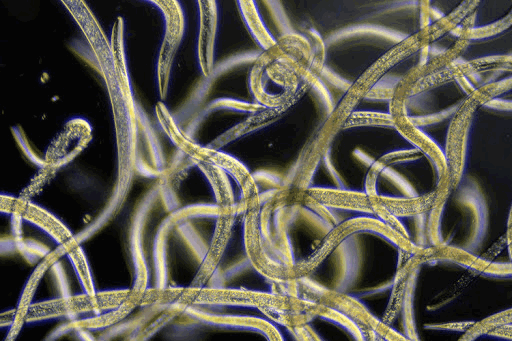

Причиной заболевания являются трипаносомы, которые в организме человека и животных приобретают продолговатую форму с ундулирующей мембраной, переходящей в жгутик. При размножении в организме насекомых, которые являются переносчиком, развиваются нетипичные криптидиальные и метациклические формы трипаносом.

Основным методом является выявление трипаносом в крови при темнопольной микроскопии или в окрашенных мазках крови. При подозрении на африканский трипаносомоз обязательно исследуют спинномозговую жидкость.

Для диагностики трипаносомоза используется световая микроскопия крови (тонкий или толстый мазок) или пунктата лимфоузла. Концентрация трипаносом в крови часто низкая, поэтому различные концентрационные методики увеличивают чувствительность диагностических методов. Серологической обследование часто неинформативно.